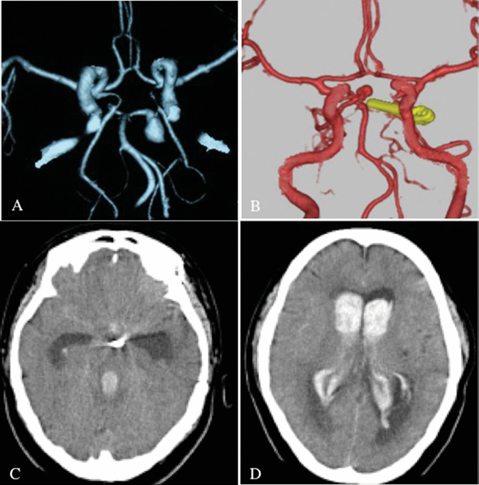

51岁的符女士曾因左侧P1梭形动脉瘤接受夹闭手术,术后恢复良好。

然而7年后,她突发剧烈头痛并陷入昏迷(Hunt-Hess 4级),CT显示弥漫性蛛网膜下腔出血伴脑室内血肿,3D-CTA揭示基底尖端新发4×4mm动脉瘤破裂。

(A)之前的3D-CTA显示左侧P1动脉瘤被夹闭;(B)3D-CTA显示基底尖端部分的先前夹子和新发动脉瘤。;(C&D)CT显示蛛网膜下腔出血伴脑室内血肿。